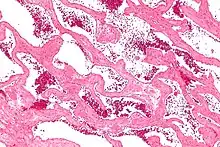

Micrograph of a cavernous liver hemangioma. H&E stain.

Cavernous hemangioma, also called cavernous angioma, venous malformation, or cavernoma,[1][2] is a type of venous malformation due to endothelial dysmorphogenesis from a lesion which is present at birth. A cavernoma in the brain is called a cerebral cavernous malformation or CCM. Despite its designation as a hemangioma, a cavernous hemangioma is not a tumor as it does not display endothelial hyperplasia. The abnormal tissue causes a slowing of blood flow through the cavities, or "caverns". The blood vessels do not form the necessary junctions with surrounding cells, and the structural support from the smooth muscle is hindered, causing leakage into the surrounding tissue. It is the leakage of blood, referred to as hemorrhage, that causes a variety of symptoms known to be associated with the condition.

Cavernous hemangiomas can arise nearly anywhere in the body where there are blood vessels. They are sometimes described as resembling raspberries because of the appearance of bubble-like caverns. Unlike capillary hemangiomas, cavernous ones can be life-threatening and do not regress.